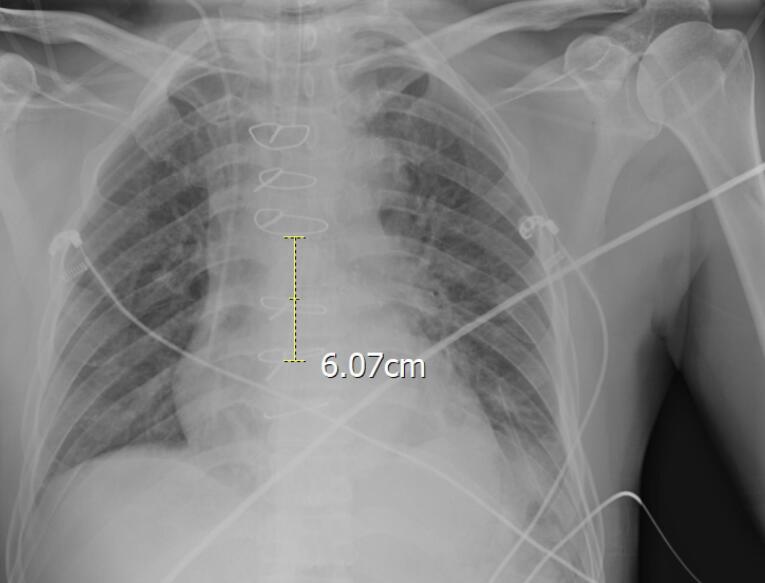

Methods: This study evaluated the reliability of the Peres formula, which estimates CVC tip placement based on patient height, within an Iranian population. A cross-sectional analysis of 100 patients undergoing cardiac surgery revealed that the Peres formula often resulted in incorrect CVC positioning, necessitating radiographic confirmation and post-insertion adjustments.

Results: The mean deviation of CVC tip placement from the ideal position near the carina was 5.13±0.78 cm. Correlation analysis highlighted significant associations between the deviation and demographic factors, including height and body mass index (BMI), suggesting the need for population-specific adjustments to the Peres formula.